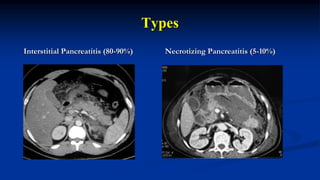

Types

Interstitial Pancreatitis (80-90%) Necrotizing Pancreatitis (5-10%)

Necrosis

Pancreatic Peri-pancreatic Combined